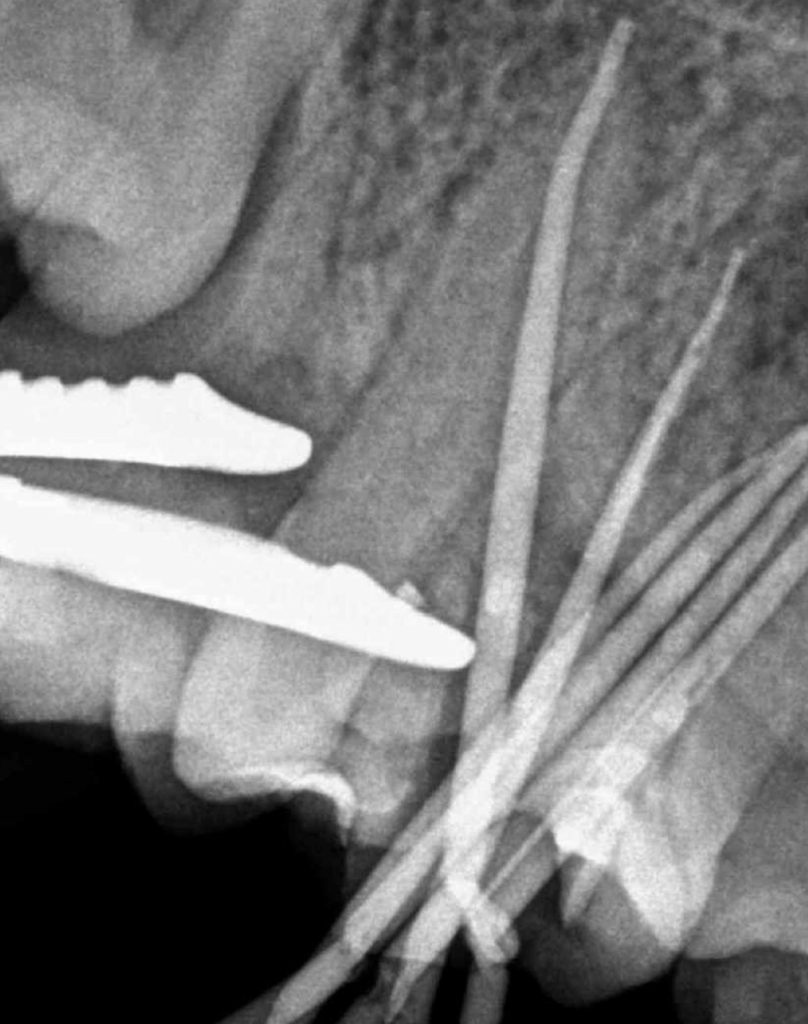

Vertical root fracture